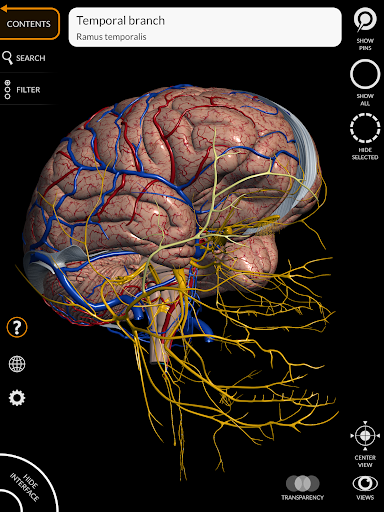

"Anatomy 3D Atlas" vous permet d'étudier l'anatomie humaine de manière simple et interactive.

Grâce à une interface simple et intuitive, il est possible d'observer chaque structure anatomique sous n'importe quel angle.

Les modèles anatomiques 3D sont particulièrement détaillés et avec des textures jusqu'à une résolution de 4k.

La subdivision par régions et les vues prédéfinies facilitent l'observation et l'étude de parties individuelles ou de groupes de systèmes et les relations entre différents organes.

MODÈLES ANATOMIQUES 3D

• Système nerveux